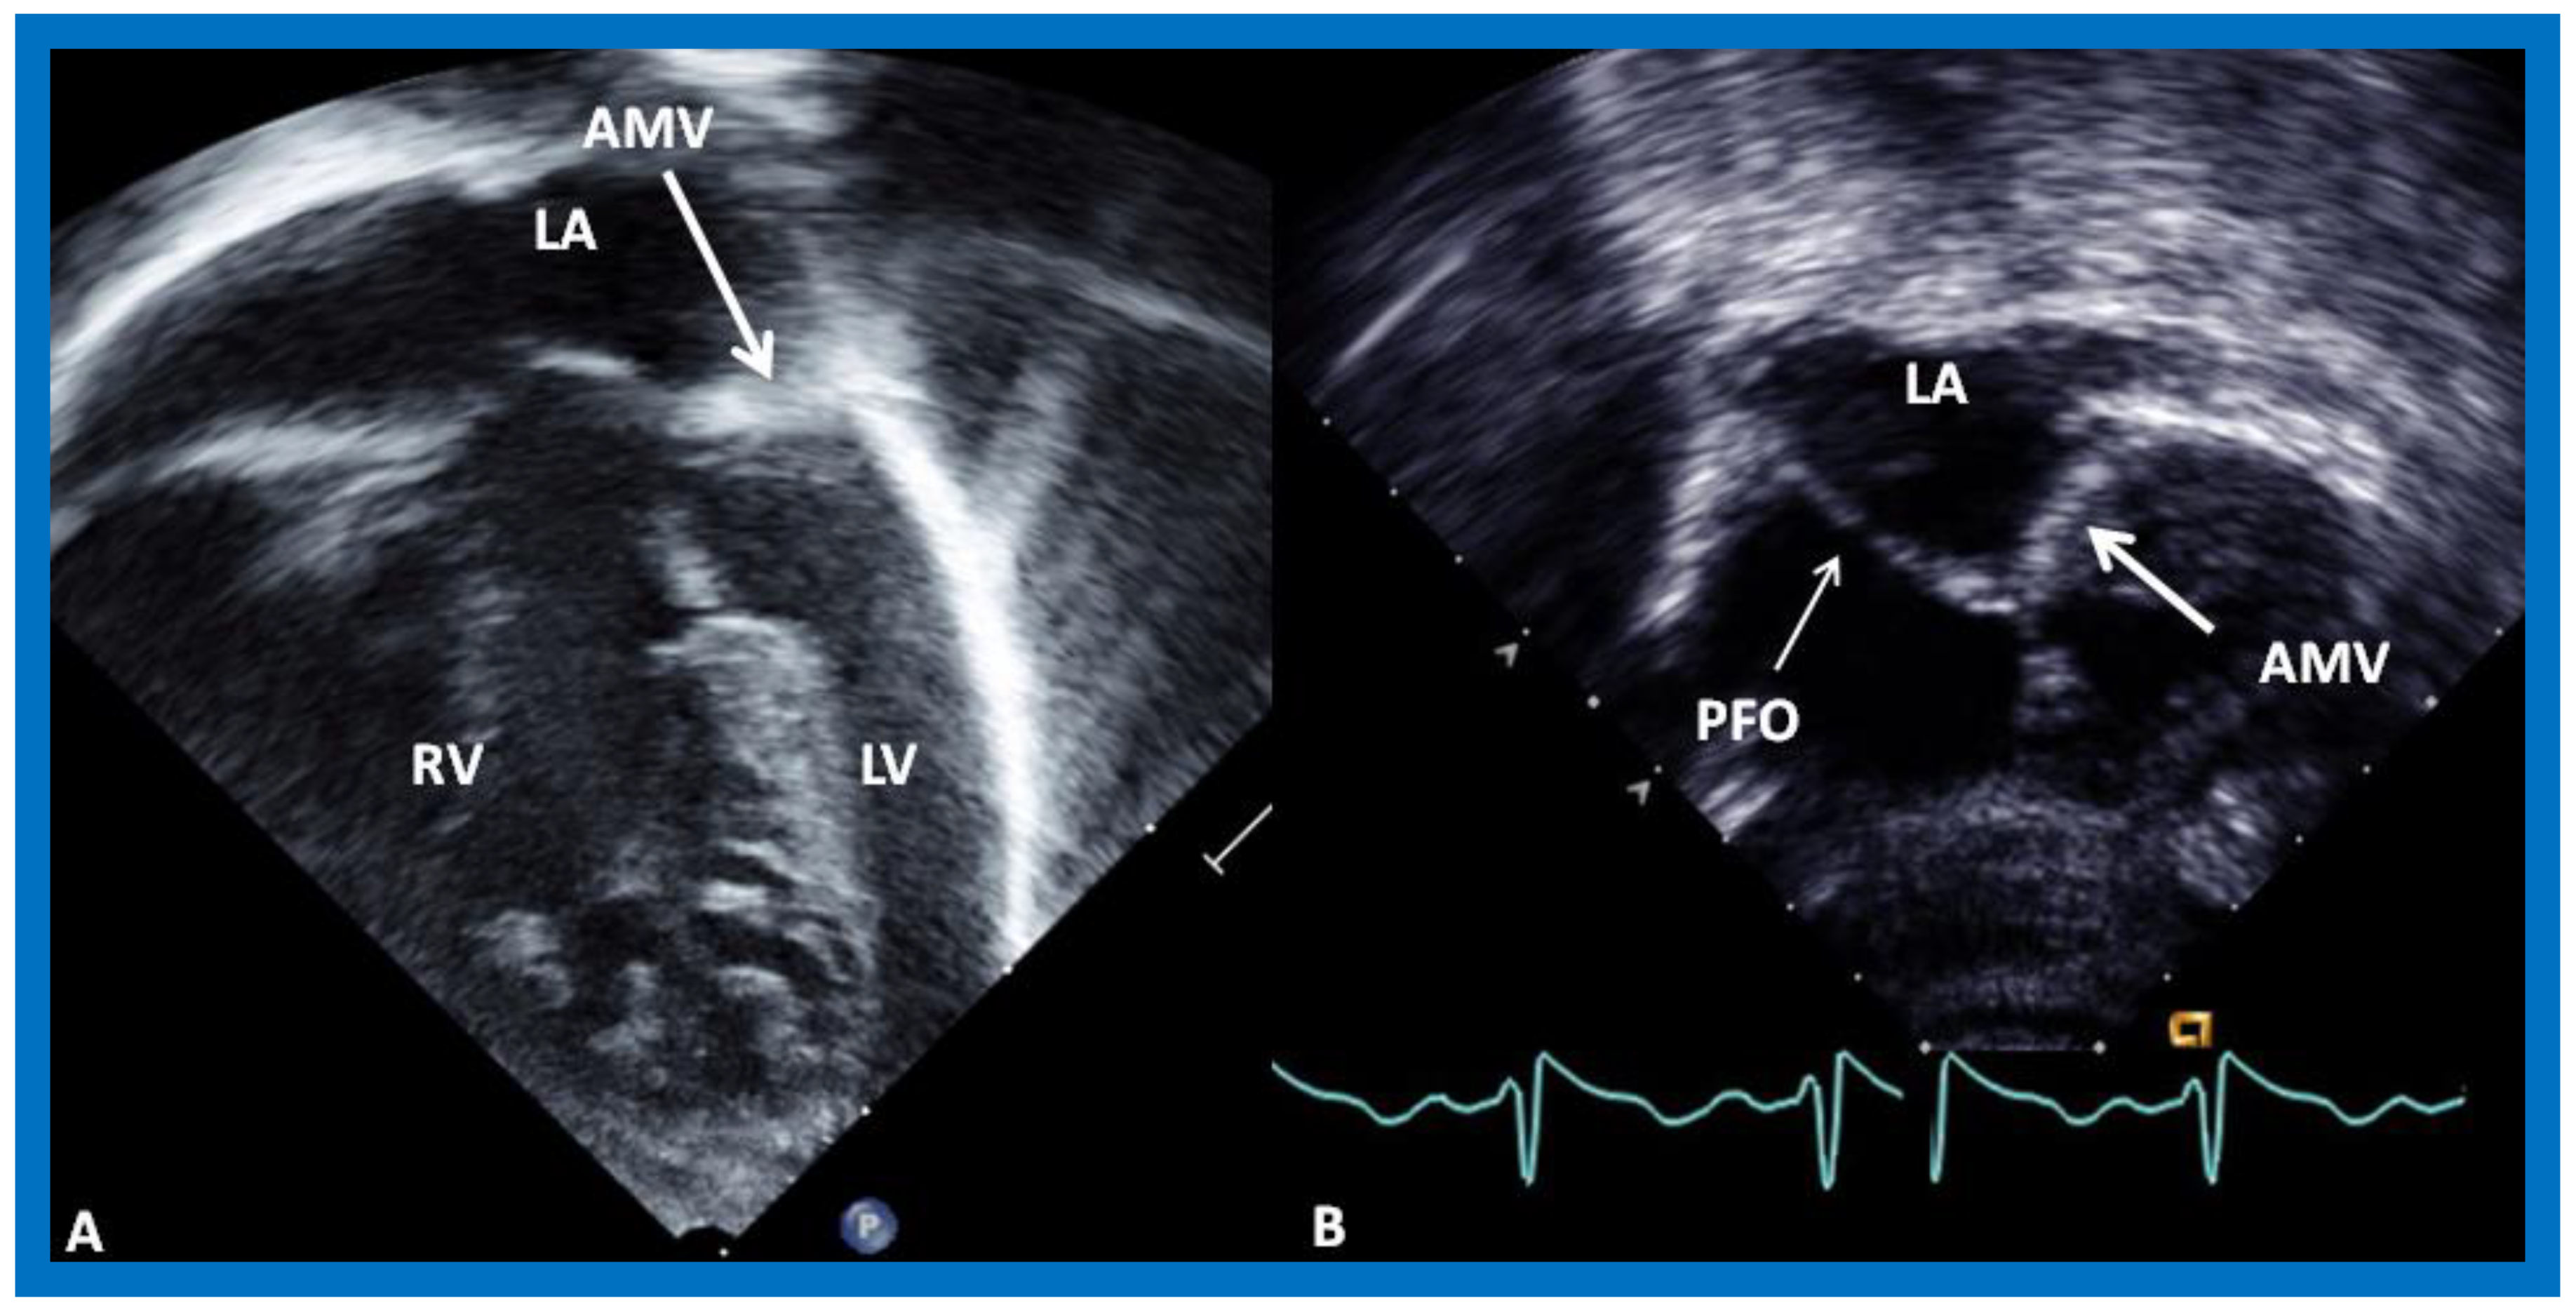

8. Echocardiogram